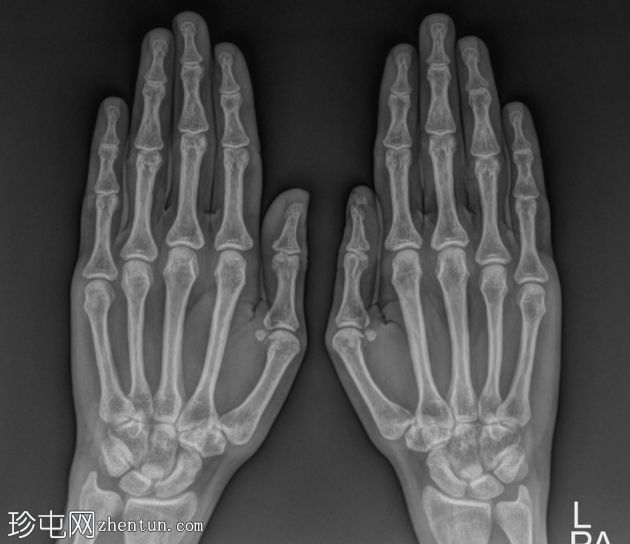

左手拇指外伤。

年龄:50岁

性别:女

X光片

正面

拇指远端指骨末端(指骨束)轻度移位骨折。

拇指远端指骨末端指骨束骨折移位。